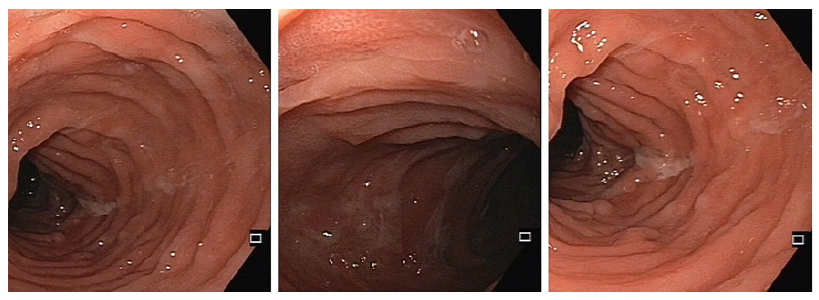

Despite initial improvement, the patient’s post-discharge assessment revealed the presence of severe fatigue and continuous diarrhoea with 2-3 bowel movements per day along with persistent microcytic anaemia, low iron stores, severe hypoalbuminemia (2.7 g/dL), and elevated faecal calprotectin (2,000 μg/g). Therefore, further investigation was deemed necessary. One month after the initial presentation, an endoscopic evaluation was conducted revealing normal mucosa in the terminal ileum but large, deep ulcerations in the ascending and transverse colon, with skip areas of normal mucosa resulting in a cobblestone-like appearance (shown in Fig. 3). The descending and sigmoid colon displayed smaller ulcers (less than 10 mm) with milder inflammation compared to the right colon. Histopathological examination revealed nonspecific findings with an intact ileal mucosal architecture with slight lymphoplasmacytic infiltrate in the lamina propria and a colonic mucosa with normal caliciform cell population without architectural distortion, despite a moderate inflammatory infiltrate, but without epithelial lymphocytosis, basal membrane thickening, granulomas, or cryptitis.

Fig. 3. Ileocolonoscopy 1 month after admission demonstrating a normal mucosa of the terminal ileum (left image) and a transverse and ascending colon with deep and large ulcers with cobblestone pattern (middle and right image).

The disparities observed among the endoscopic findings, histopathological results, and MRE evaluation did not permit a conclusive diagnosis. Consequently, a subsequent endoscopic reassessment was conducted. This follow-up evaluation revealed substantial improvement, characterized by the absence of ulcerations and restoration of the typical vascular pattern of the colonic mucosa. Additionally, evidence of scar tissue from prior ulcerations was noted (shown in Fig. 4). Histopathology demonstrated preserved architecture, accompanied by oedema, vascular congestion, and mild inflammatory infiltrate yet no evidence of granulomas. Culture and polymerase chain reaction analyses yielded negative results for Mycobacterium tuberculosis. No stool or biopsy cultures were conducted to detect YE infection since the diagnostic yield was expected to be low at this time.

Fig. 4. Ileocolonoscopy 3 months following the initial admission demonstrating complete resolution of the endoscopic pattern with some cicatricial areas of previous deep ulcers (middle image).